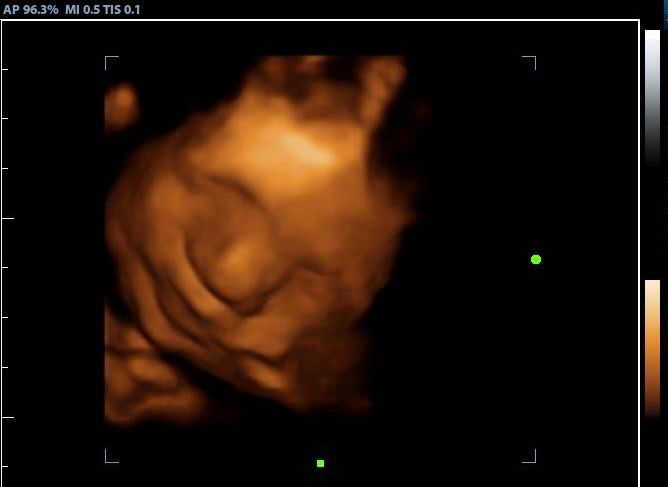

2d, 3d,4d & HD live

Enjoy a private, affordable ultrasound from the comfort of your home, perfect for moms between 7–41 weeks. Share the moment with loved ones by connecting directly to your TV for real-time viewing in 2D, 3D, or 4D. Ideal for baby showers or gender reveal parties!